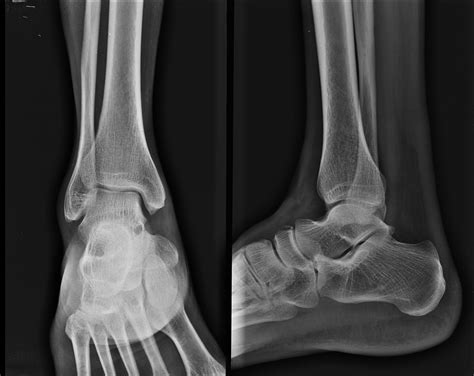

Talus Bone Fracture Nhs at Michelle Ma blog